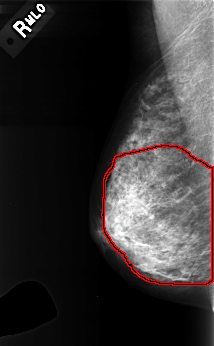

FILE: C_0366_1.RIGHT_MLO.OVERLAY

TOTAL_ABNORMALITIES 1

ABNORMALITY 1

LESION_TYPE CALCIFICATION TYPE PLEOMORPHIC DISTRIBUTION DIFFUSELY_SCATTERED

ASSESSMENT 3

SUBTLETY 3

PATHOLOGY BENIGN

TOTAL_OUTLINES 1

BOUNDARY